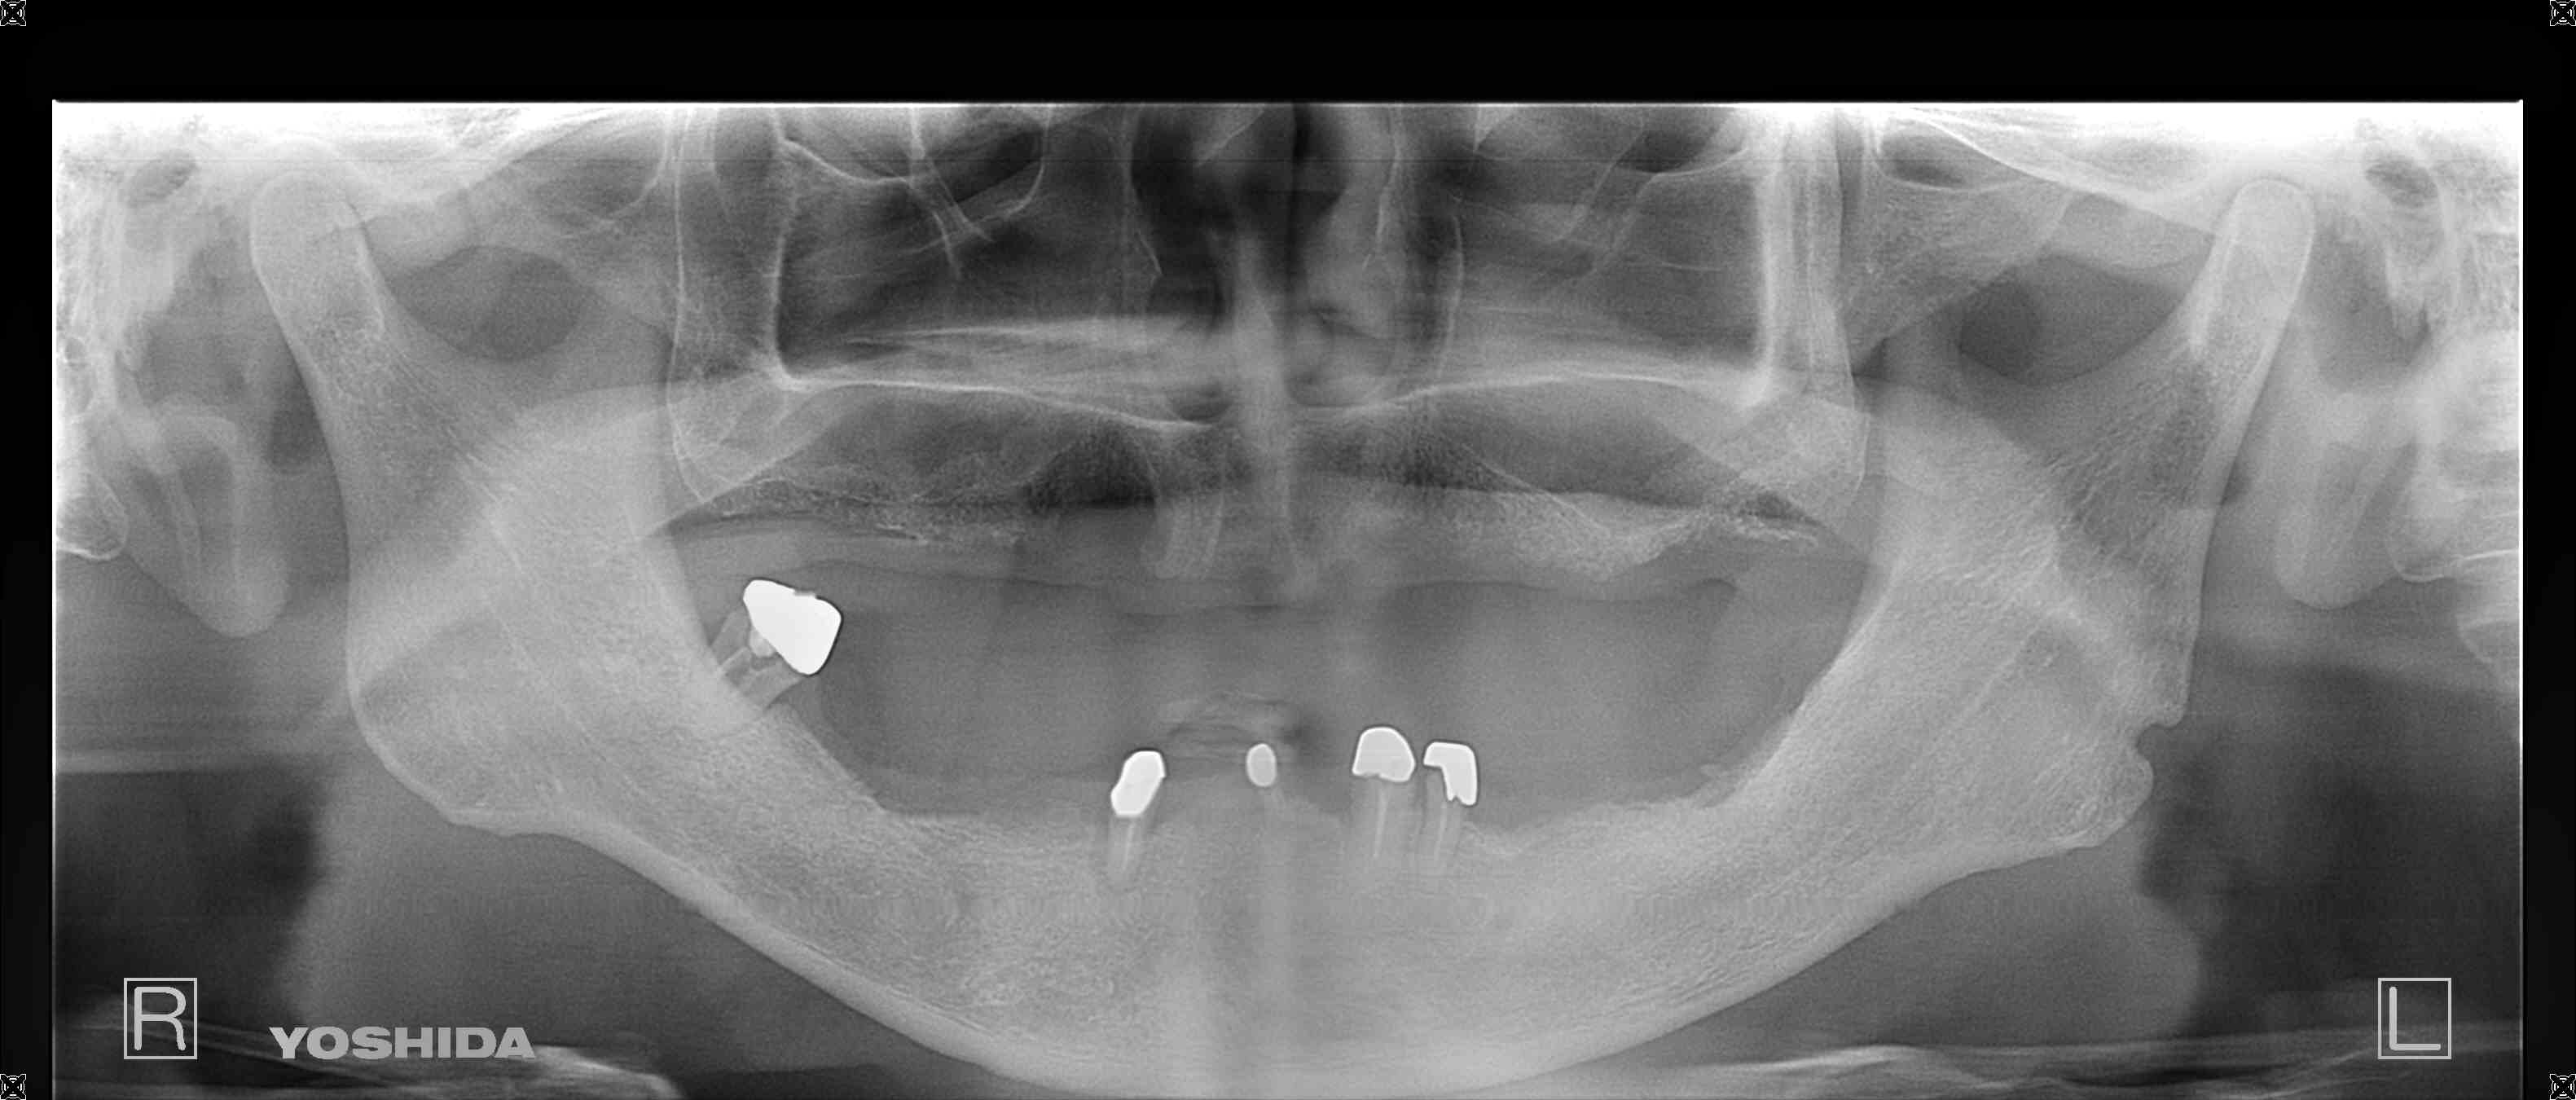

こちらは、三木市にお住まいの70代男性患者様のレントゲン写真で、上下の入れ歯の不調を主訴として来院された際のものです。

上顎はすべての歯を喪失されており、総義歯(フルデンチャー)を装着されていました。下顎には、残存歯を支えとする義歯(オーバーデンチャー)を装着されていましたが、歯周病の進行により下顎の歯が著しく動揺し、抜歯が不可避の状態でした。